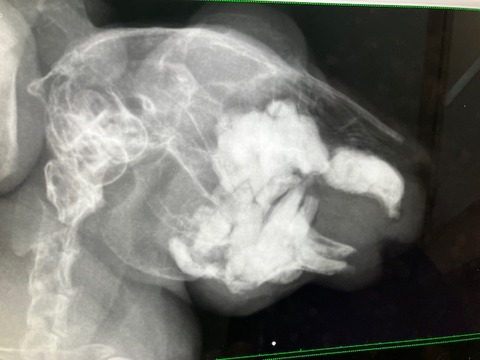

レントゲンなどは当初の去勢手術以降、機会がなかったので、

血液検査とともにしっかり健診させていただきました。

レントゲン

歯根への影響も見られず、共に良好でした